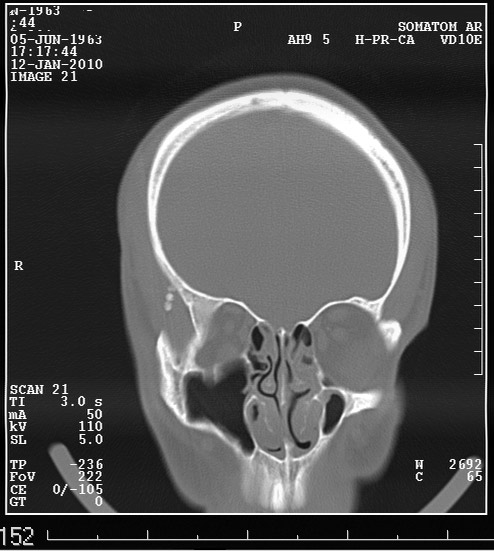

Выкладываю данные КТ

На снимке утолщение веретенообразное мышечного слоя с наличием кальцификатов(два) Кальцификаты в мышце чаще встречаются при паразитарных инфекциях(трихиниллез,токсоплазмоз,цистецеркоз),но их больше по количеству и в разных местах.Оссифицирующий миозит-имеет свою картину и распространение.Насчет Хортона-навряд ли,это же поражение сосуда.Насчет тофусов-они содержат ураты,чаще локализуются подкожно(не в мышце),при подагре осификации вдоль сухожилий.А может был удар,гематома с частичной кальцификацией?